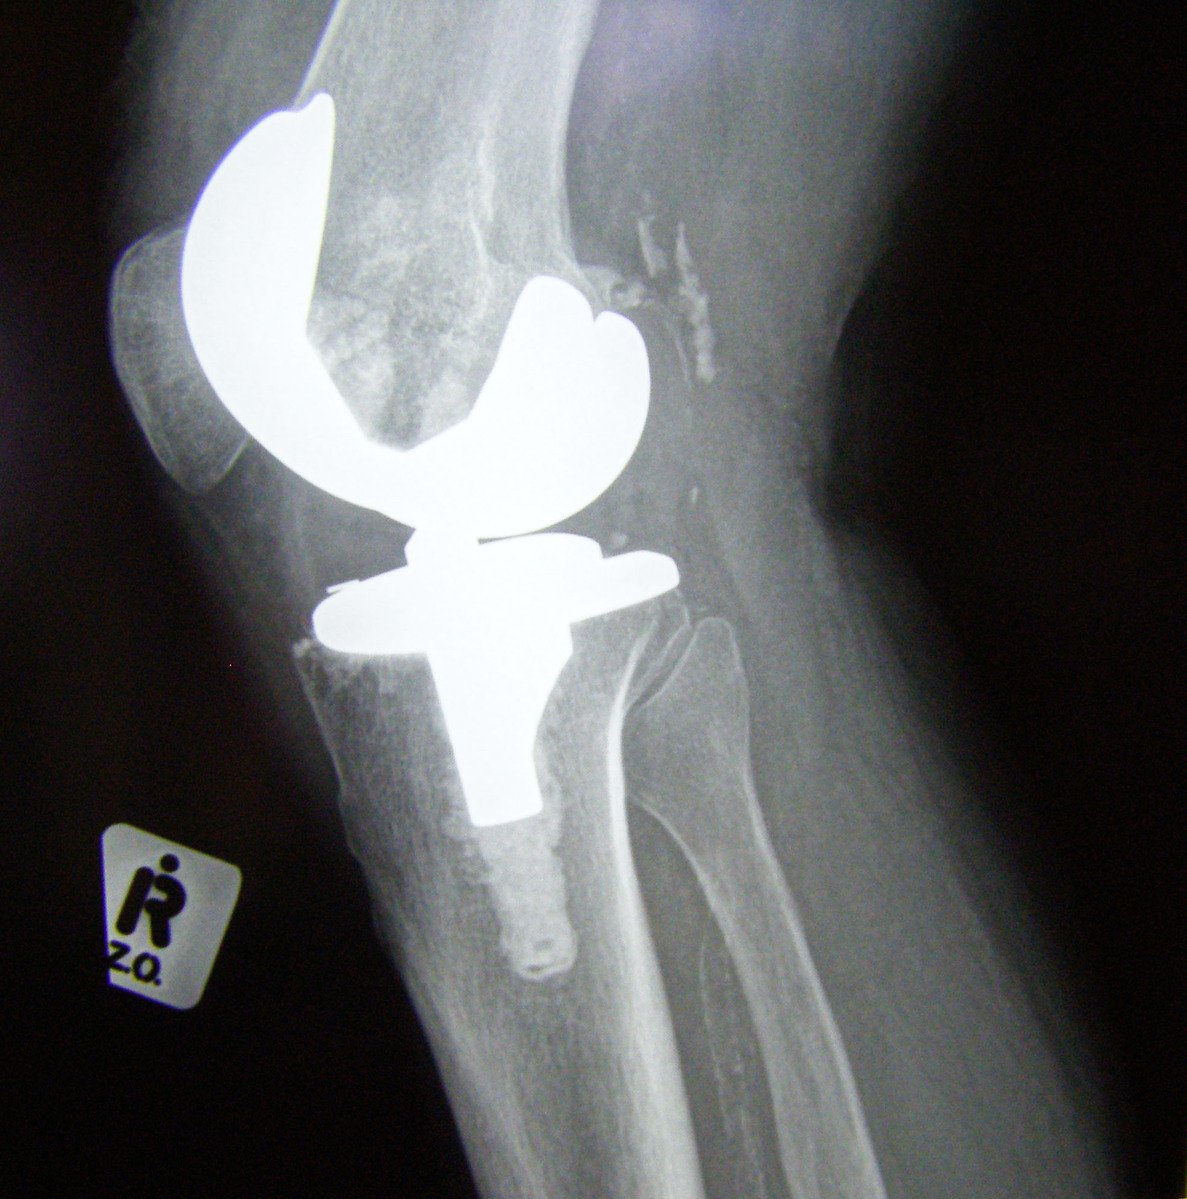

The surgery, which can be done in Pacific Surgical Center’s outpatient clinic, can improve quality of life and help regain or maintain mobility. Experts at the Mayo Clinic describe the process; “The procedure involves cutting away damaged bone and cartilage from your thighbone, shinbone and kneecap and replacing it with an artificial joint (prosthesis) made of metal alloys, high-grade plastics and polymers. In determining whether a knee replacement is right for you, an orthopedic surgeon assesses your knee’s range of motion, stability, and strength. X-rays help determine the extent of damage.”